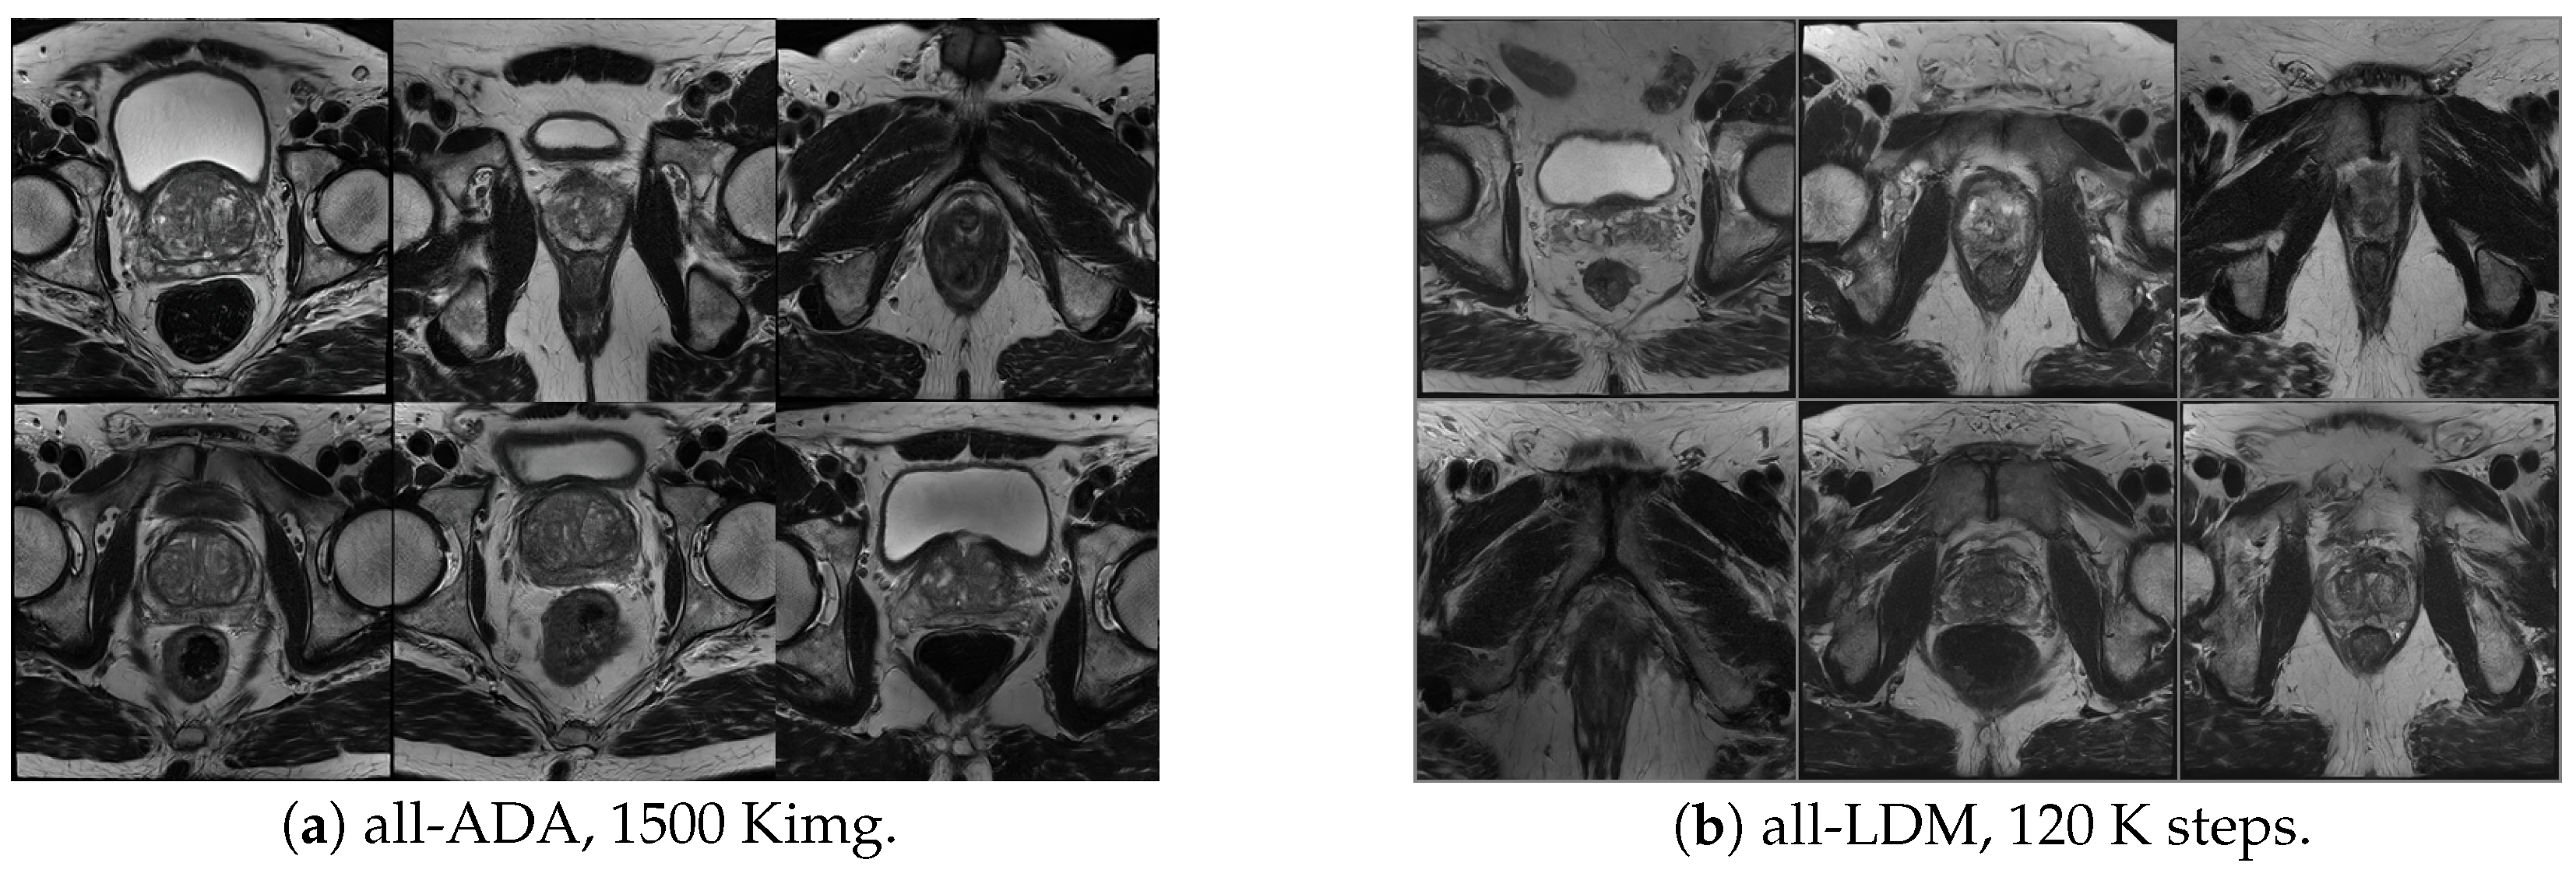

Quantitative results are reported in Table A1, showing consistently lower FID and KID and higher P G R for StyleGAN2-ADA across both full-dataset and class-specific training regimes. Compared to the all-NoAug variant, the ADA-based model achieved substantially improved distribution alignment, reducing FID from 15.22 to 10.43 and KID from 0.0106 to 0.0062. While Precision remained comparable between the two configurations, Recall was markedly higher with ADA (0.166 vs. 0.0819), indicating improved coverage of the real data distribution and reduced mode collapse. Similar trends were observed in the class-specific experiments, where ADA consistently outperformed LDM-based alternatives. Qualitative examples illustrating these differences are shown in Figure A1, where StyleGAN2-ADA samples exhibit sharper gland boundaries and more coherent textures compared to those generated by the LDM.

Figure A1. 2D slice-level qualitative comparison. (a) Samples generated by StyleGAN2-ADA (all-ADA model) after 1500 kimg of training. (b) Samples generated by the LDM model (all-LDM model) after 120 K training steps. StyleGAN2-ADA produces sharper gland boundaries and more coherent textures than the LDM.